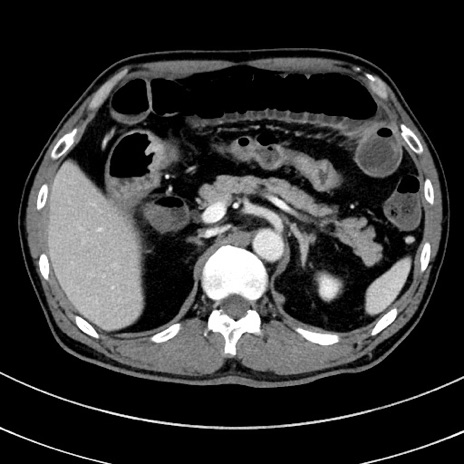

症例8(横断像)

【症例】 60歳代男性

【主訴】 黒色吐物

【現病歴】 4日前から嘔気自覚、2日前の朝食後にも嘔気あり、自分で手で嘔吐反射起こし嘔吐したところ血が混ざっていたため受診。

【既往歴】 5年前汎発性腹膜炎を伴う急性虫垂炎で手術、高血圧、前立腺肥大症、高脂血症

【身体所見】 腹部正中に手術癩痕あり 腹部平坦・軟圧痛なし膨満感あり

【データ】WBC 8400、CRP 4.54